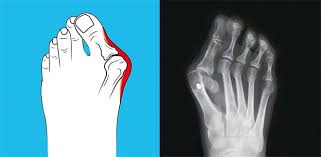

Halluks Valgus Ayak Resimleri

halluks valgus resim